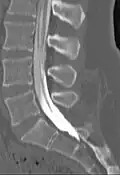

Myelogram showing arachnoiditis in the lumbar spine. | |

Myelography is a type of radiographic examination that uses a contrast medium (e.g. iodised oil[1]) to detect pathology of the spinal cord, including the location of a spinal cord injury, cysts, and tumors. Historically the procedure involved the injection of a radiocontrast agent into the cervical or lumbar spine, followed by several X-ray projections. Today, myelography has largely been replaced by the use of MRI scans, although the technique is still sometimes used under certain circumstances – though now usually in conjunction with CT rather than X-ray projections.[2]